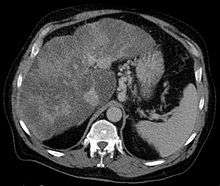

| Isolated gastric varices of Sarin classification IGV-1 seen on gastroscopy in a patient with portal hypertension | |

The Sarin classification of gastric varices identifies four different anatomical types of gastric varices, which differ in terms of treatment modalities.